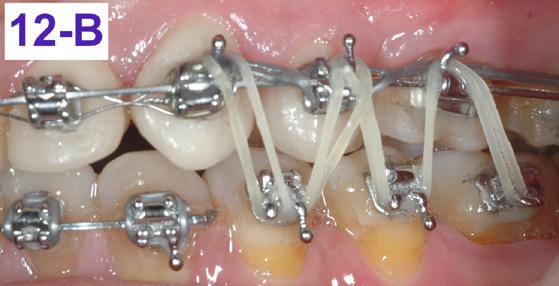

cut and bent in, just distally to the cuspids. Also, two 3/8” – 2.5 oz. elastics were placed, in a letter “W” with tail configuration, for one month. They were zig-zagged from the maxillary cuspids and finished on the mandibular molars and had a slightly protrusive line of action on the mandible (Figure 12 - A, B).10

FIG. oral mucosa FIG. 9C: Tissue guard, right lateral view FIG. 9D: Protraction of the first molar, left lateral view FIG. 10A: Lingual intra – Power thread, occlusal view FIG. 10B: Class II elastic, right lateral view FIG. 10C: Triangular elastic, left lateral view FIG. FIG. FIG. 12A: “W” with tail, right lateral view FIG. 12B: “W” with tail, left lateral view